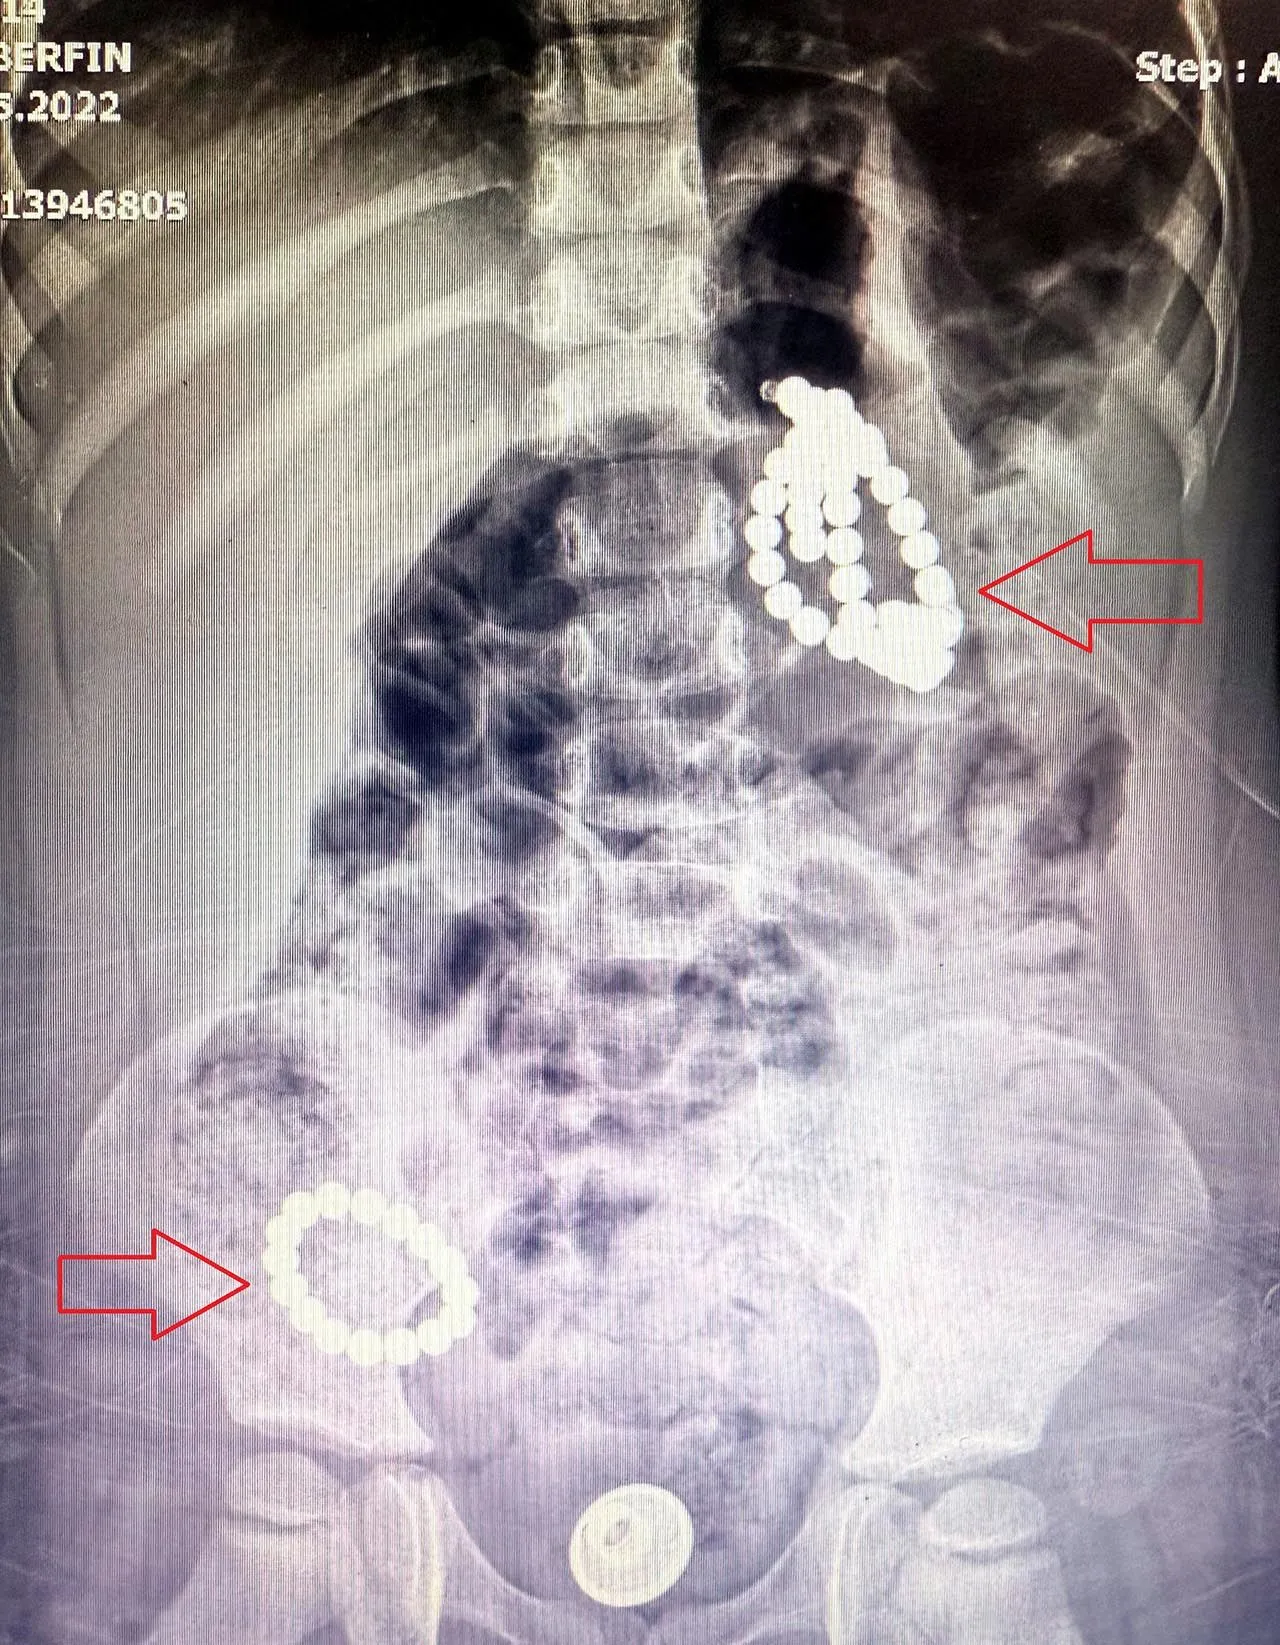

Aile kızlarının kolye ya da bileklik yuttuğunu düşünürken, doktorlar manyetik boncuklardan şüphelendi. Önce takip edilmek üzere yatışı yapılan çocuğun, yabancı cisimleri dışkı yoluyla atması beklendi. Ancak cisimlerin sabit kaldığı anlaşılınca manyetizma tespit edebilen bir program yardımıyla durumun ciddiyeti anlaşıldı. Yuttuğu cisimlerin mıknatıslı boncuk olduğu anlaşılan Berfin, acilen ameliyata alındı ve Çocuk Cerrahi ve Gastroenteroloji ekiplerinin birlikte girdiği 5 saat süren ameliyatla sindirim sisteminden 66 adet manyetik boncuk çıkarıldı. Endoskopi sırasında midede 3, bağırsaklarda 2 delinme ve yapışıklık da tespit edildi. Edinilen bilgiye göre yaklaşık 7 aydır vücutta bulunduğu düşünülen boncuklar, organları birbirine yapıştırmış ve ciddi hasara yol açtı.Boncuklar çıkarıldı, delinmeler laparoskopik yöntemle onarıldı. Baba Mahmut N., oyuncak olarak satılan boncukların yasaklanması gerektiğini belirtirken, "Bu bir oyuncak değil, ölüm tuzağıymış" diye konuştu.